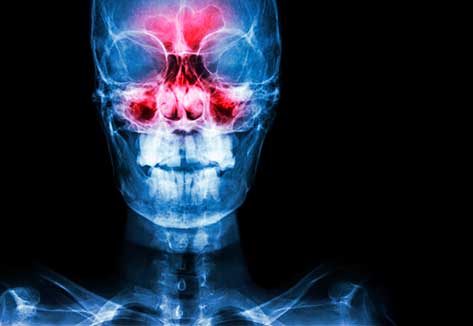

Types of Nasal Cancer

Nasal cancer, also called sinus cancer or Sinonasal Adenocarcinoma, is a potentially fatal condition that affects approximately 10 people per million.

Nasal cancer tumors may develop in the nasal cavity as well as in the ethmoid or maxillary sinuses. The following are among the most common types of nasal cancer: